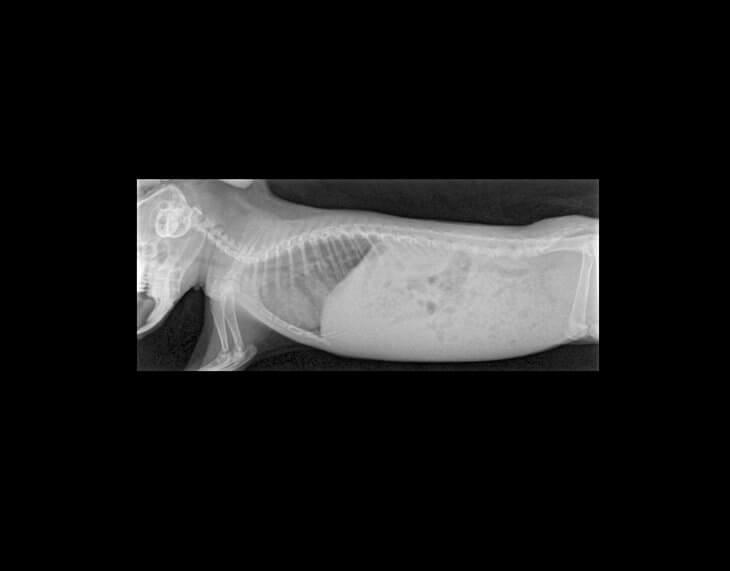

En el cas de l’Audrey, es va recomanar realitzar un cultiu fúngic i una radiografia, ja que les nostres sospites principals eren que patia algun procés respiratori i una infecció de la pell causada per fongs (dermatofitosi).

Una vegada realitzades les proves, es varen confirmar les nostres sospites. Audrey patia una dermatofitosi juntament amb una pneumònia localizada al pulmó dret.